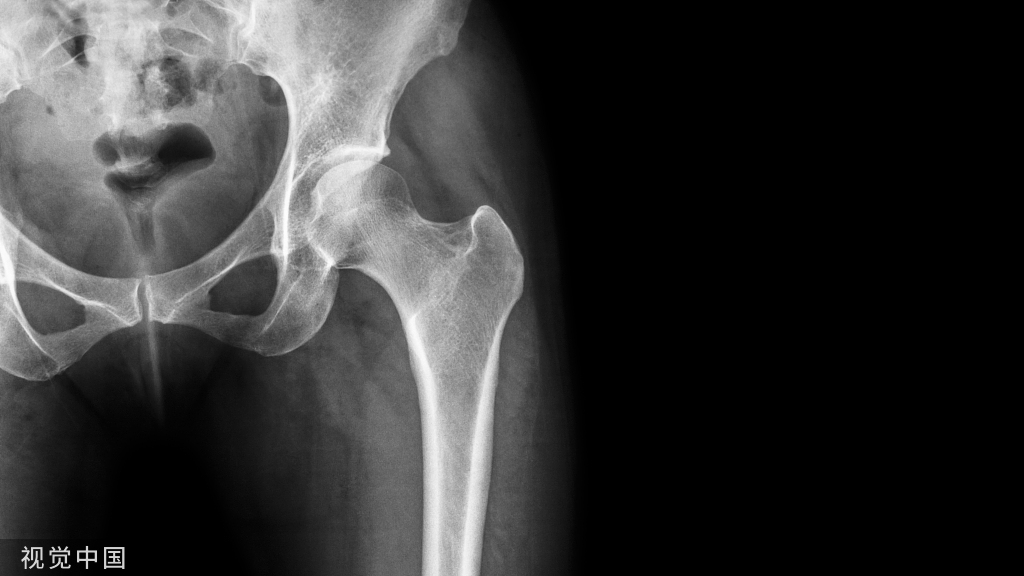

1.骨折时损伤有一定的报道提示骨盆骨折时该血管断裂损伤,尤其是在耻骨支外4-6cm处骨折时需要注意。

一个老年女性患者骨盆骨折,没有移位,住院后给予保守治疗后出院,出院三天后在上厕所时,腹部疼痛、尿少、心动过速、血压减低,立即入院后查体发现下腹部疼痛,压痛反跳痛,腹膜炎表现。

行CT,发现腹腔有10*10*15的血肿位于耻骨骨折旁边。